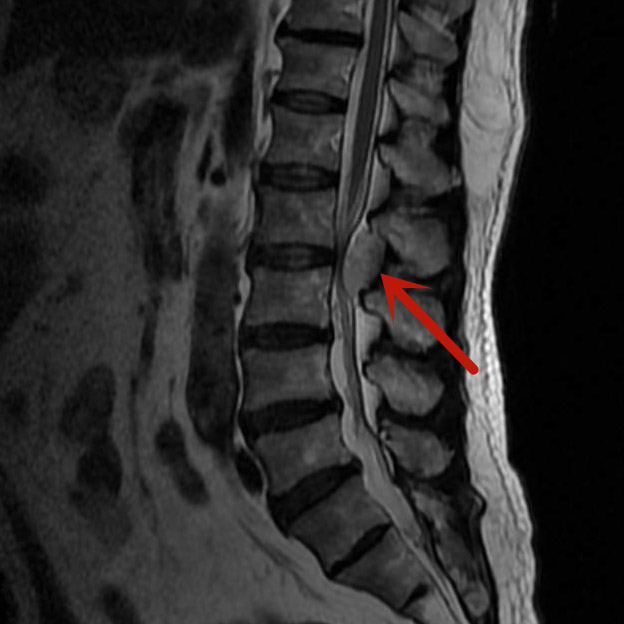

梁先生因雙下肢麻木來我院就診,經(jīng)磁共振檢查發(fā)現(xiàn)是腰椎管內(nèi)血管瘤在作怪,若不及時(shí)手術(shù)治療,隨著腫瘤的生長(zhǎng)、神經(jīng)長(zhǎng)時(shí)間受壓,將可能導(dǎo)致雙下肢癱瘓、大小便失禁等嚴(yán)重后果。

經(jīng)我院脊柱骨科醫(yī)療團(tuán)隊(duì)研究后,決定對(duì)梁先生實(shí)施內(nèi)鏡下腰椎管內(nèi)腫瘤切除術(shù),腫瘤約3.5cm×1.5cm大小,別看腫瘤不大,但要完全通過0.8cm大小切口在內(nèi)鏡下切除,腫瘤后方的椎板切除減壓、腫瘤與周圍神經(jīng)的分離、腫瘤的暴露、腫瘤的徹底切除,這都需要嫻熟的內(nèi)鏡操作技術(shù)。

在完善術(shù)前檢查,排除手術(shù)禁忌,充分做好術(shù)前準(zhǔn)備后,由微創(chuàng)手術(shù)經(jīng)驗(yàn)豐富的醫(yī)師主刀,經(jīng)過兩個(gè)小時(shí),完整將腫瘤切除。梁先生術(shù)后第一天便可下床活動(dòng),四天后即康復(fù)出院。